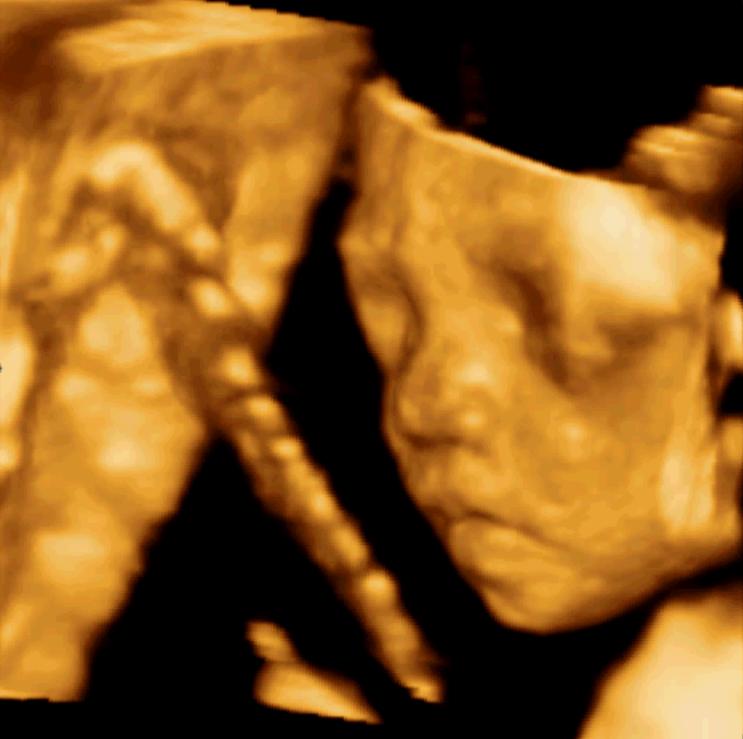

看見胎兒

下午帶老婆去做了4維彩超,終於看見孩子的腦袋和手腳了。男女尚不可知,不過知道全須全尾,健健康康,也就很開心了。

加油,寶貝,再有三個月就出生啦!